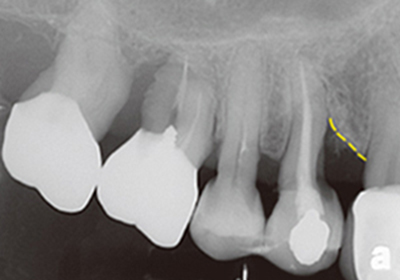

案例3

補骨前

補骨後